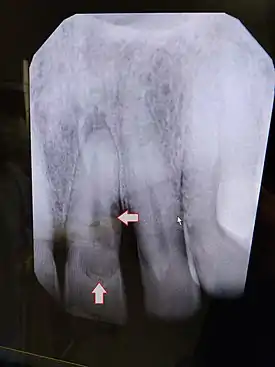

| Post traumatic External tooth resorption 9 | |

It may also present as an incidental, radiographic finding. Radiographically, a radiolucent area of uniform density within the root canal may be visible with well-defined borders. Canal walls may appear sclerosed, thus the outline of pulp chambers or root canals may not be followed through the lesion. Lesions may also be oval radiolucencies that are continuous with the canal walls.

External Inflammatory Root Resorption

External inflammatory root resorption may be caused by trauma to the root surface, due to damage to the periodontal ligament (PDL) and/or extended drying following tooth avulsion. Following trauma, dentinal tubules are exposed leading to communication with an infective or necrotic pulp. This leads to an inflammatory process that causes external root resorption.[16]